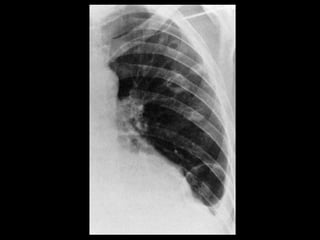

Infarto Pulmonar Estárelacionado à obstrução tromboembólica de uma artéria pulmonar de tamanho médio e implica necrose do tecido pulmonar; Os achados radiológicos clássicos incluem o sinal de Westermark(hipoperfusão focal) e a corcova de Hampton(densidade periférica em formato triangular acima do diafragma); TC: atelectasia seg ou subsegmentar e atenuação focal mal definida em vidro fosco ou consolidação parenquimatosa(periférica e triangular).